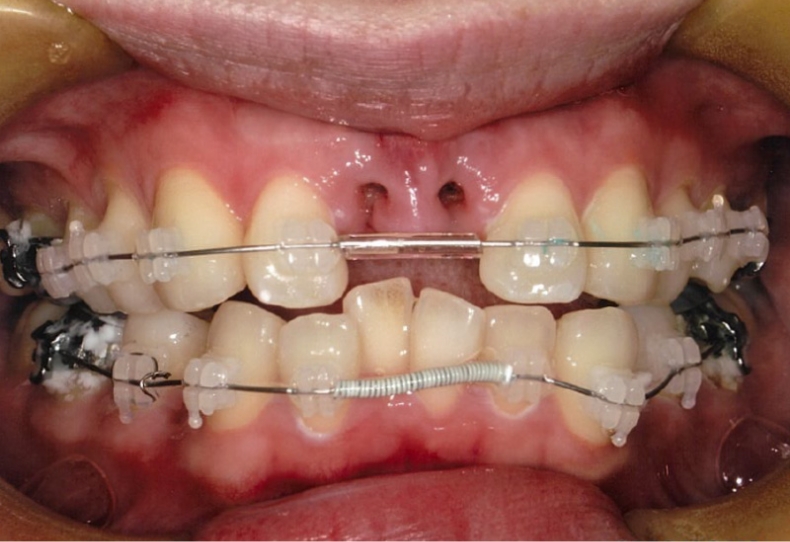

Case1 / 前歯2本の欠損

治療前

| 主訴 | 幼少期の事故による前歯2本の欠損 |

|---|---|

| 治療内容 | 3D-LST矯正治療法を用いて、欠損部分のスペースを適切に調整し、噛み合わせも改善 |

| 患者年代・治療期間 | 20代女性・3年2ヶ月(難治症例) |